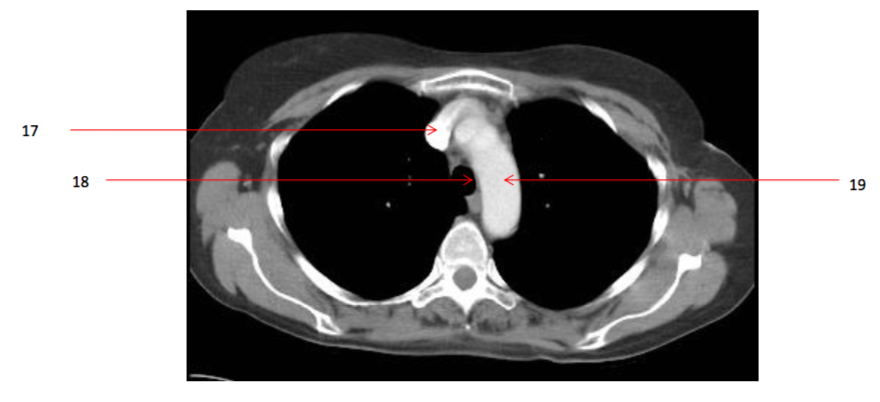

Number 19?

Arch of aorta

Number 17?

SVC

Number 20?

Ascending aorta

Number 18?

trachea